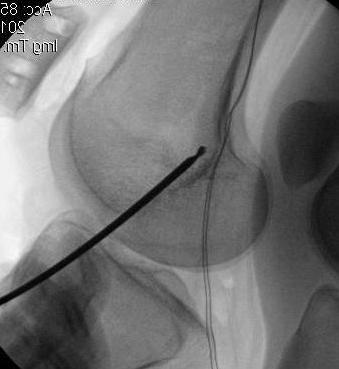

2. Perform TTT (if TTTG > 20)

- incision over TTT

- medialise at least 1 cm

- ensure some element of Fulkerson / anteriorise

- can distalise if patella alta

- secure with screws (2 x small fragment usually sufficient)

- reassess stability